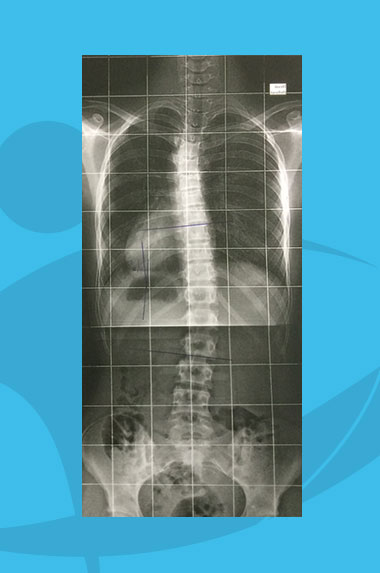

Cobb (angle de) :

angle formé par les 2 parallèles aux plateaux des vertèbres les plus inclinées sur l’horizontal aux extrémités de la courbure scoliotique.

Test de Risser :

test permettant d’apprécier la maturité osseuse au niveau des crêtes iliaques